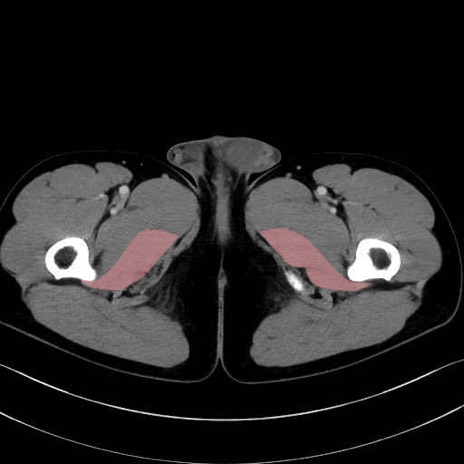

大内転筋(Adductor magnus)、小内転筋(Adductor minimus) のCT画像の解剖

大内転筋・小内転筋 (Adductor magnus / Adductor minimus)